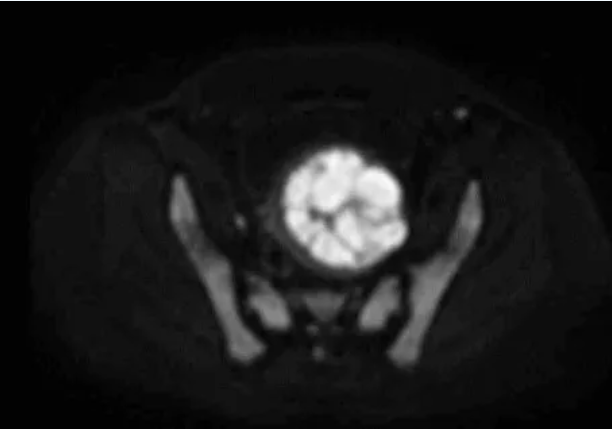

术前MRI平扫及增强扫描可鉴别子宫肌瘤与隐匿性子宫平滑肌肉瘤。弥散加权成像(DWI)高信号、表观弥散系数(ADC)低信号及强化不均是子宫肉瘤的典型影像学表现;MRI的T2加权成像(T2WI)信号可评估消融难度,若T2WI高信号则提示肌瘤含水量高,消融难度通常大于T2WI低信号的病灶。

图:DWI显示高信号强度、